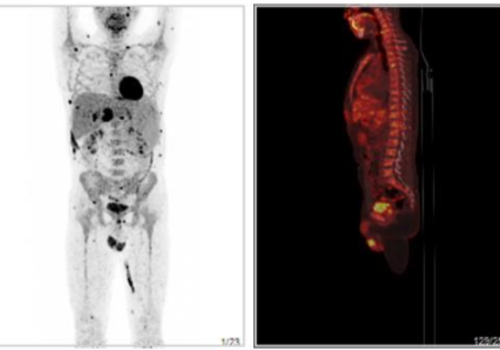

淋巴瘤治疗后复查,做PETCT检查案例-全国PETCT/MR检查预约网-癌症筛查-肿瘤复查-高端体检简要病史:患者2014年反复发热,未明确诊断,同时发现脾脏增大。2018.1右腰部肿物穿刺病理提示淋巴样细胞异常增生,肿瘤性病变不能除外,结合免疫组化考虑以T细胞性非霍奇金淋巴瘤首先考虑。后病理会诊考虑T淋巴样细胞弥漫浸润,考虑外周T细胞性非霍奇金淋巴瘤。2018.5反复发热,后行化疗8次,末次化疗结束时间为2019. 1。自述2018. 10外院PET评估病情好转。近2个月发现有下胸部皮下无痛性肿块,自觉变化不大。B超检查提示局部脂肪水肿。2020. 3发热一次,抗感染治疗后好转。1周前胸部CT未见明显异常。诊断结果:1.淋巴瘤治疗后,全身皮下脂肪间隙、肌肉及其间隙多发结节、骨髓不均匀FDG代谢异常增高,结合病史,考虑为淋巴瘤所致;腹盆腔内脂肪组织FDG代谢不均句轻度异常增高,结合病史,考虑为淋巴瘤浸润不除外。2.脾大。3.左肺下叶胸膜下斑片影,未见FDG代谢异常增高,考虑为炎性可能大,建议CT定期随访;双肺小结节,未见FDG代谢异常增高,建议随访;右肺少许纤维灶。4.脂肪肝;结肠炎;痔疮。5.椎体骨质增生。